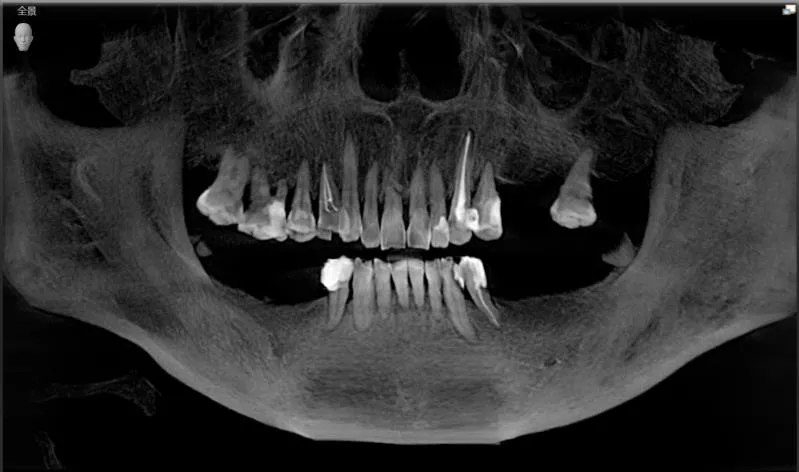

阿姨术前口内CBCT全景照

曹申主任为阿姨进行了数字化的会诊,借助Sirona CBCT全景影像信息和相关修复信息为基础,借助数字化专业种植设计软件进行术前诊断和种植方案规划。